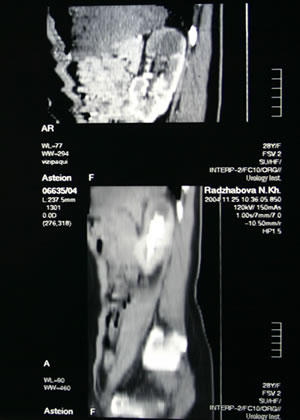

КОМПЬЮТЕРНАЯ

ТОМОГРАФИЯ: |

|